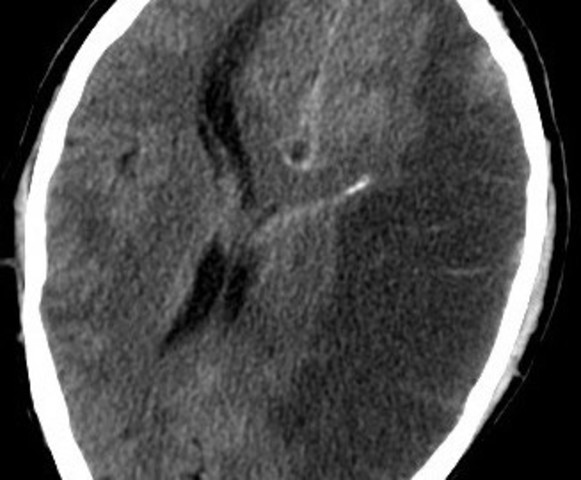

• Lesiones Isquemicas

Lesiones Isquemicas

se define como una reducción, o ausencia completa de la irrigación sanguínea puede ser: Isquemia Global: , cuando el flujo sanguíneo es insuficiente para cubrir las demandas metabólicas del cerebro, causado por un paro cardíaco, una isquemia prolongada conduce al infarto. Isquemia Focal:se produce cuando un coágulo de sangre ha ocluido un vaso cerebral lo que reduce el flujo de sangre a una región específica aumentando el riesgo de muerte celular, causada por trombosis o embolia